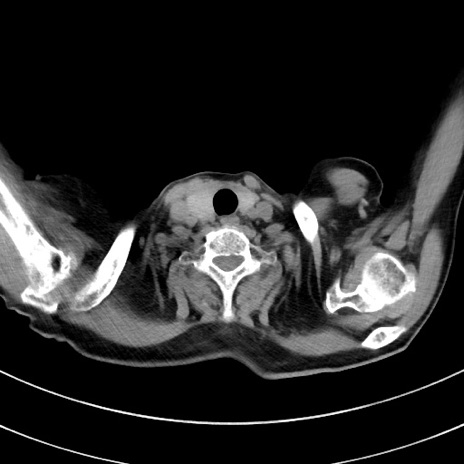

症例33(横断像)

【症例】70歳代 女性

【主訴】心窩部痛

【現病歴】延髄病変の精査・加療にて神経内科入院中。本日より心窩部痛あり。

【既往歴】虫垂炎

【身体所見】右下腹部を中心に圧痛と反跳痛あり。

【データ】WBC 10900、CRP 0.02